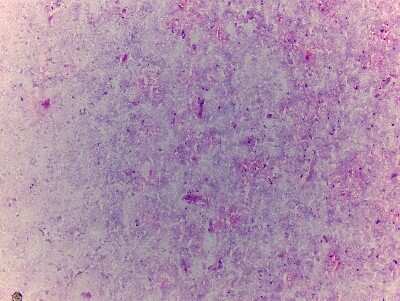

8 results for "Brain Postcentral Gyrus Slides and MicroArrays" in Products

Brain Postcentral Gyrus: Slides and MicroArrays